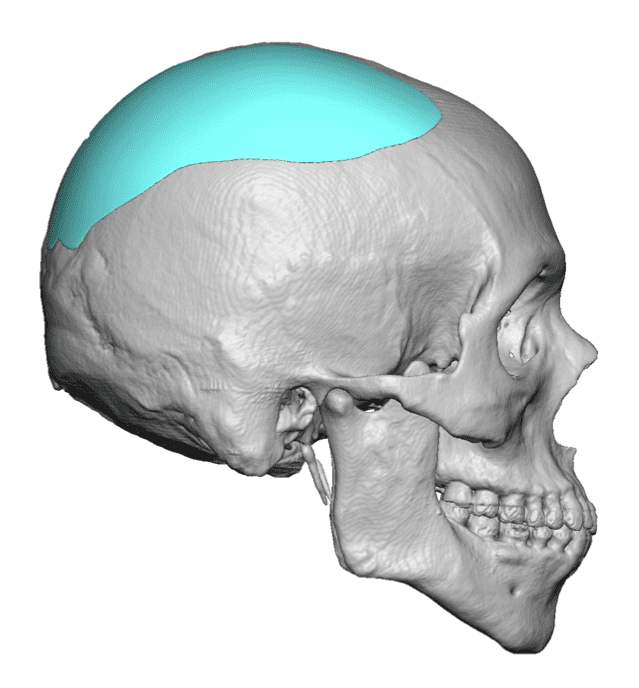

Desire for a higher and more prominent crown of the skull.

Crown of skull augmentation using a custom skull implant.

Desire for a higher and more prominent crown of the skull.

Crown of skull augmentation using a custom skull implant.